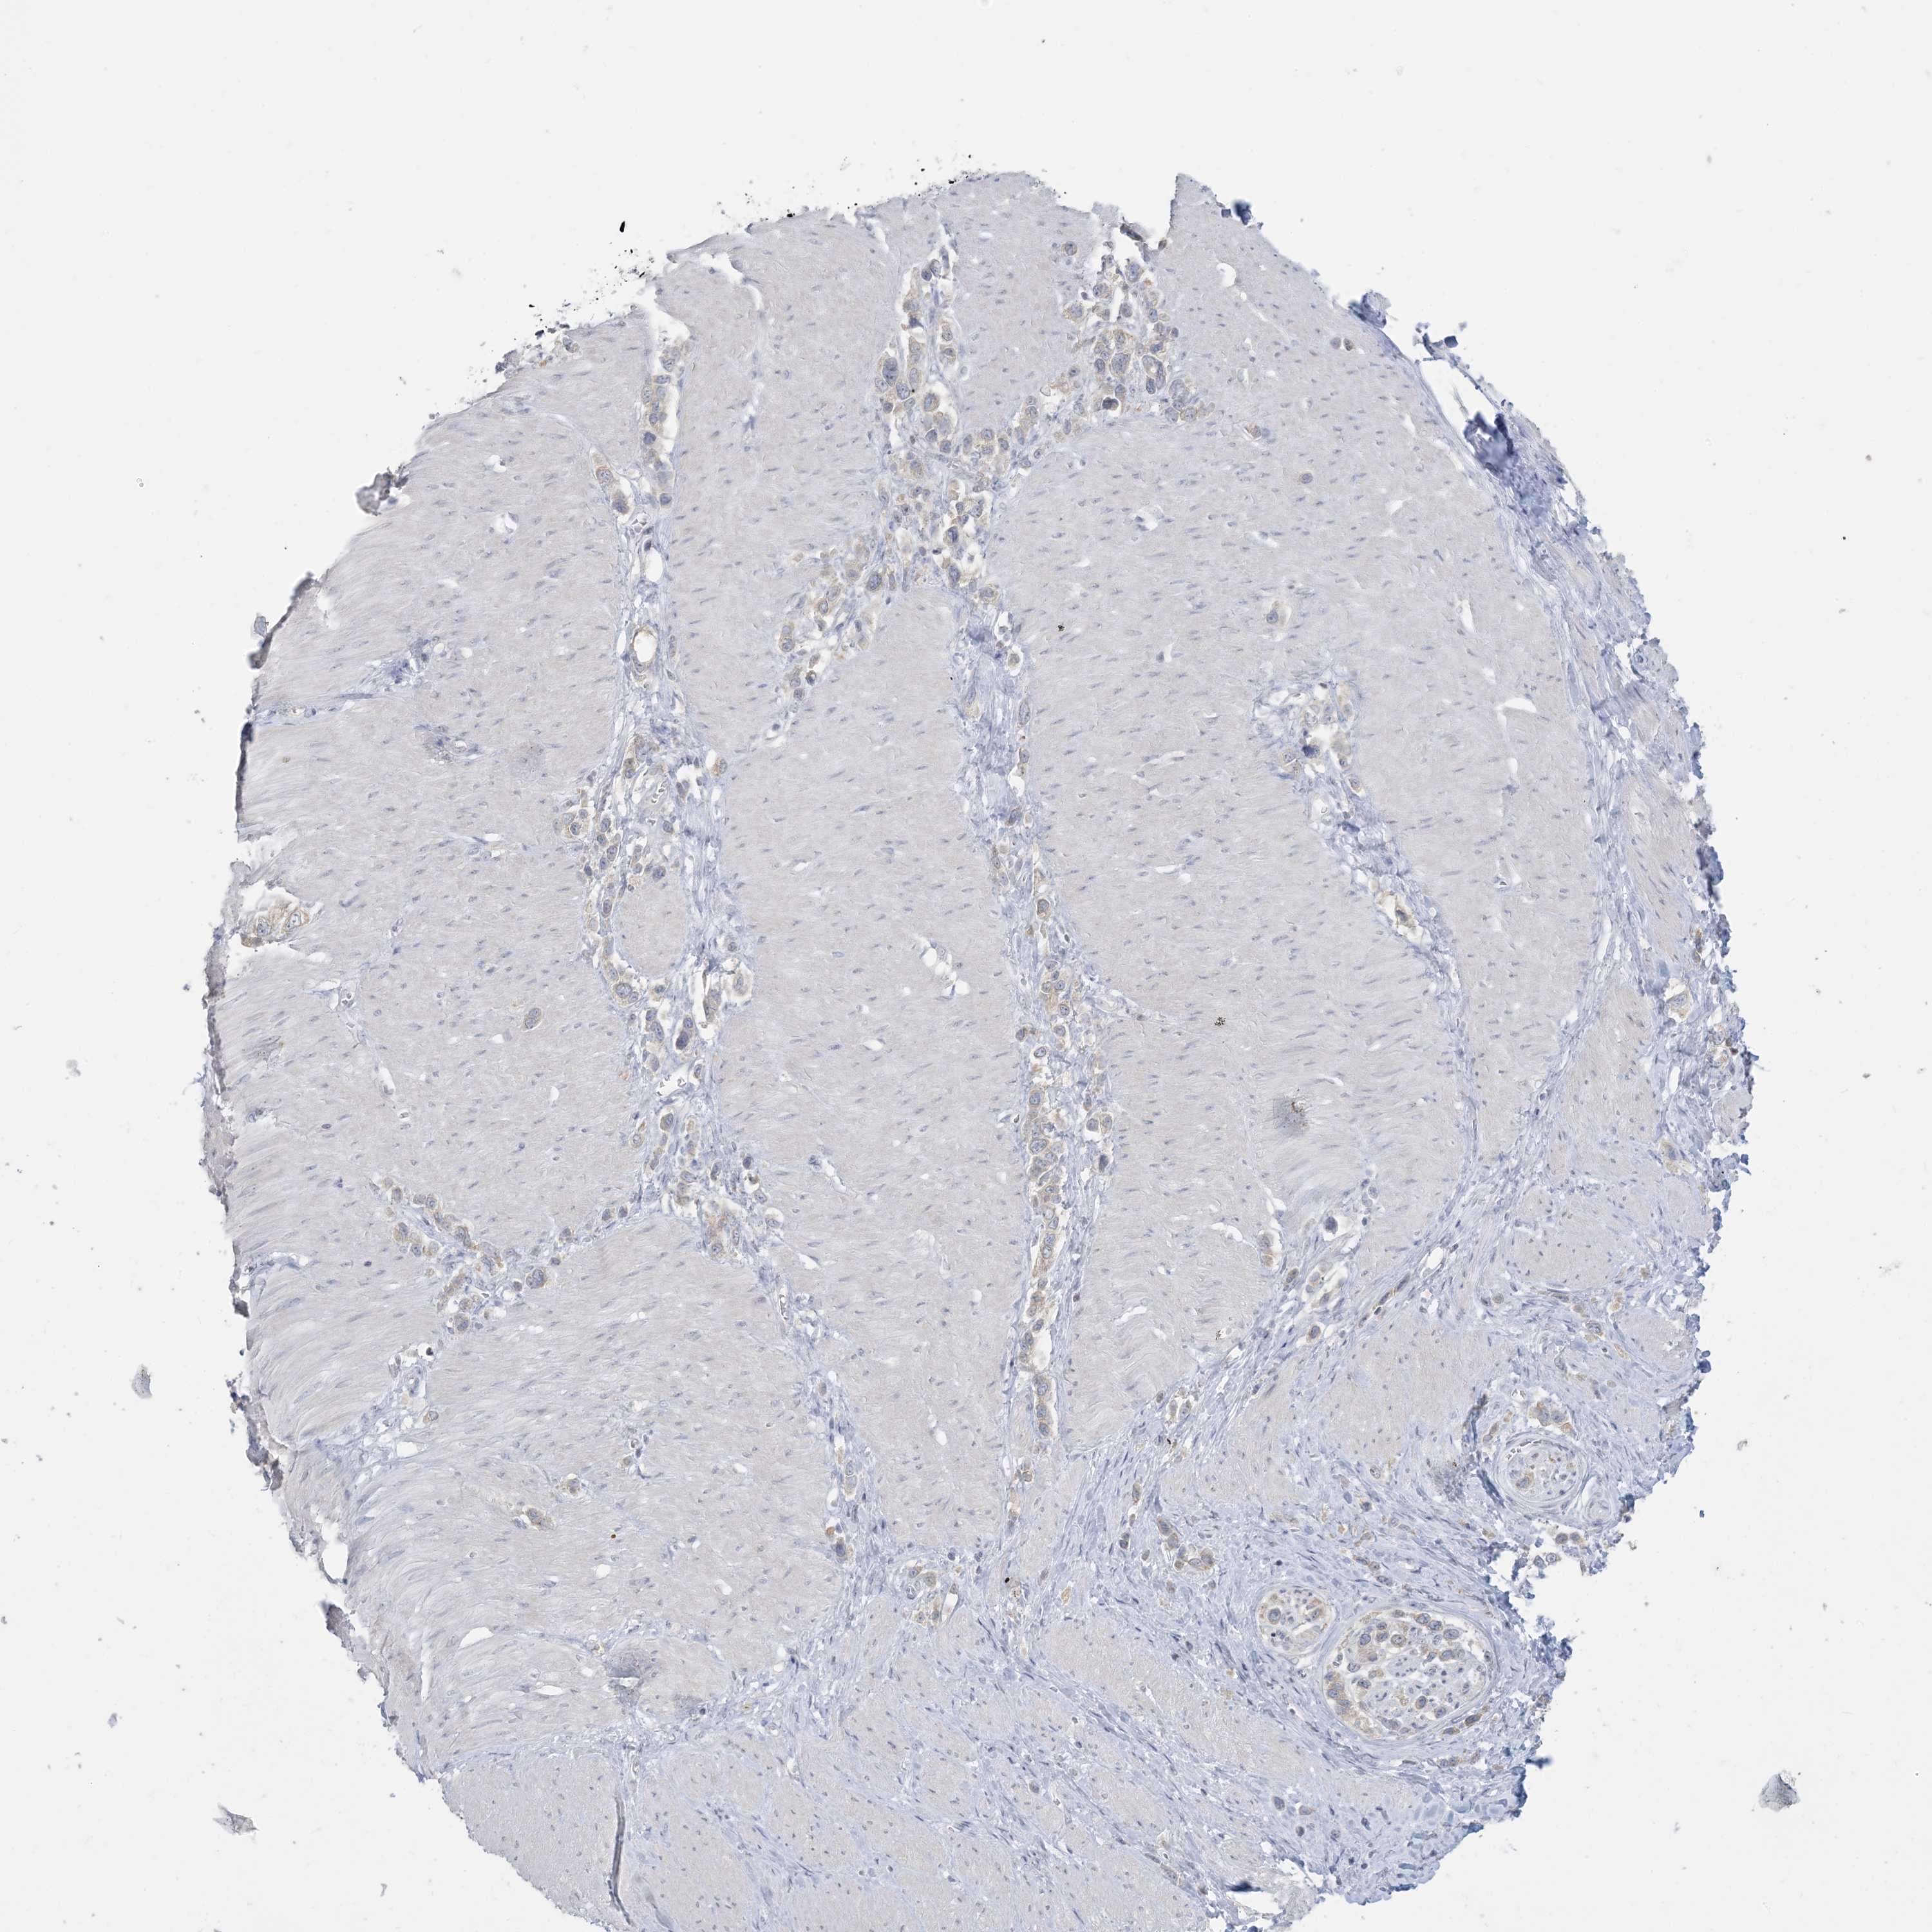

STOMACH CANCER - Protein expressioni

A mouse-over function shows sample information and annotation data. Click on an image to view it in a full screen mode. Samples can be filtered based on level of antibody staining by selecting one or several of the following categories: high, medium, low and not detected. The assay and annotation is described here.

Note that samples used for immunohistochemistry by the Human Protein Atlas do not correspond to samples in the TCGA dataset.

Antibody stainingi

Antibody staining in the annotated cell types in the current human tissue is reported as not detected, low, medium, or high, based on conventional immunohistochemistry profiling in selected tissues. This score is based on the combination of the staining intensity and fraction of stained cells.

Each image is clickable and will lead to virtual microscopy that enables deeper exploration of all samples and also displays staining intensity scores, fraction scores and subcellular localization as well as patient and tissue information for each sample.

Antibody CAB037085

Staining

High

Medium

Low

Not detected

Intensity

Strong

Moderate

Weak

Negative

Quantity

>75%

75%-25%

<25%

None

Location

Nuclear

Cytoplasmic/membranous

Cytoplasmic/membranous,nuclear

Adenocarcinoma, NOS